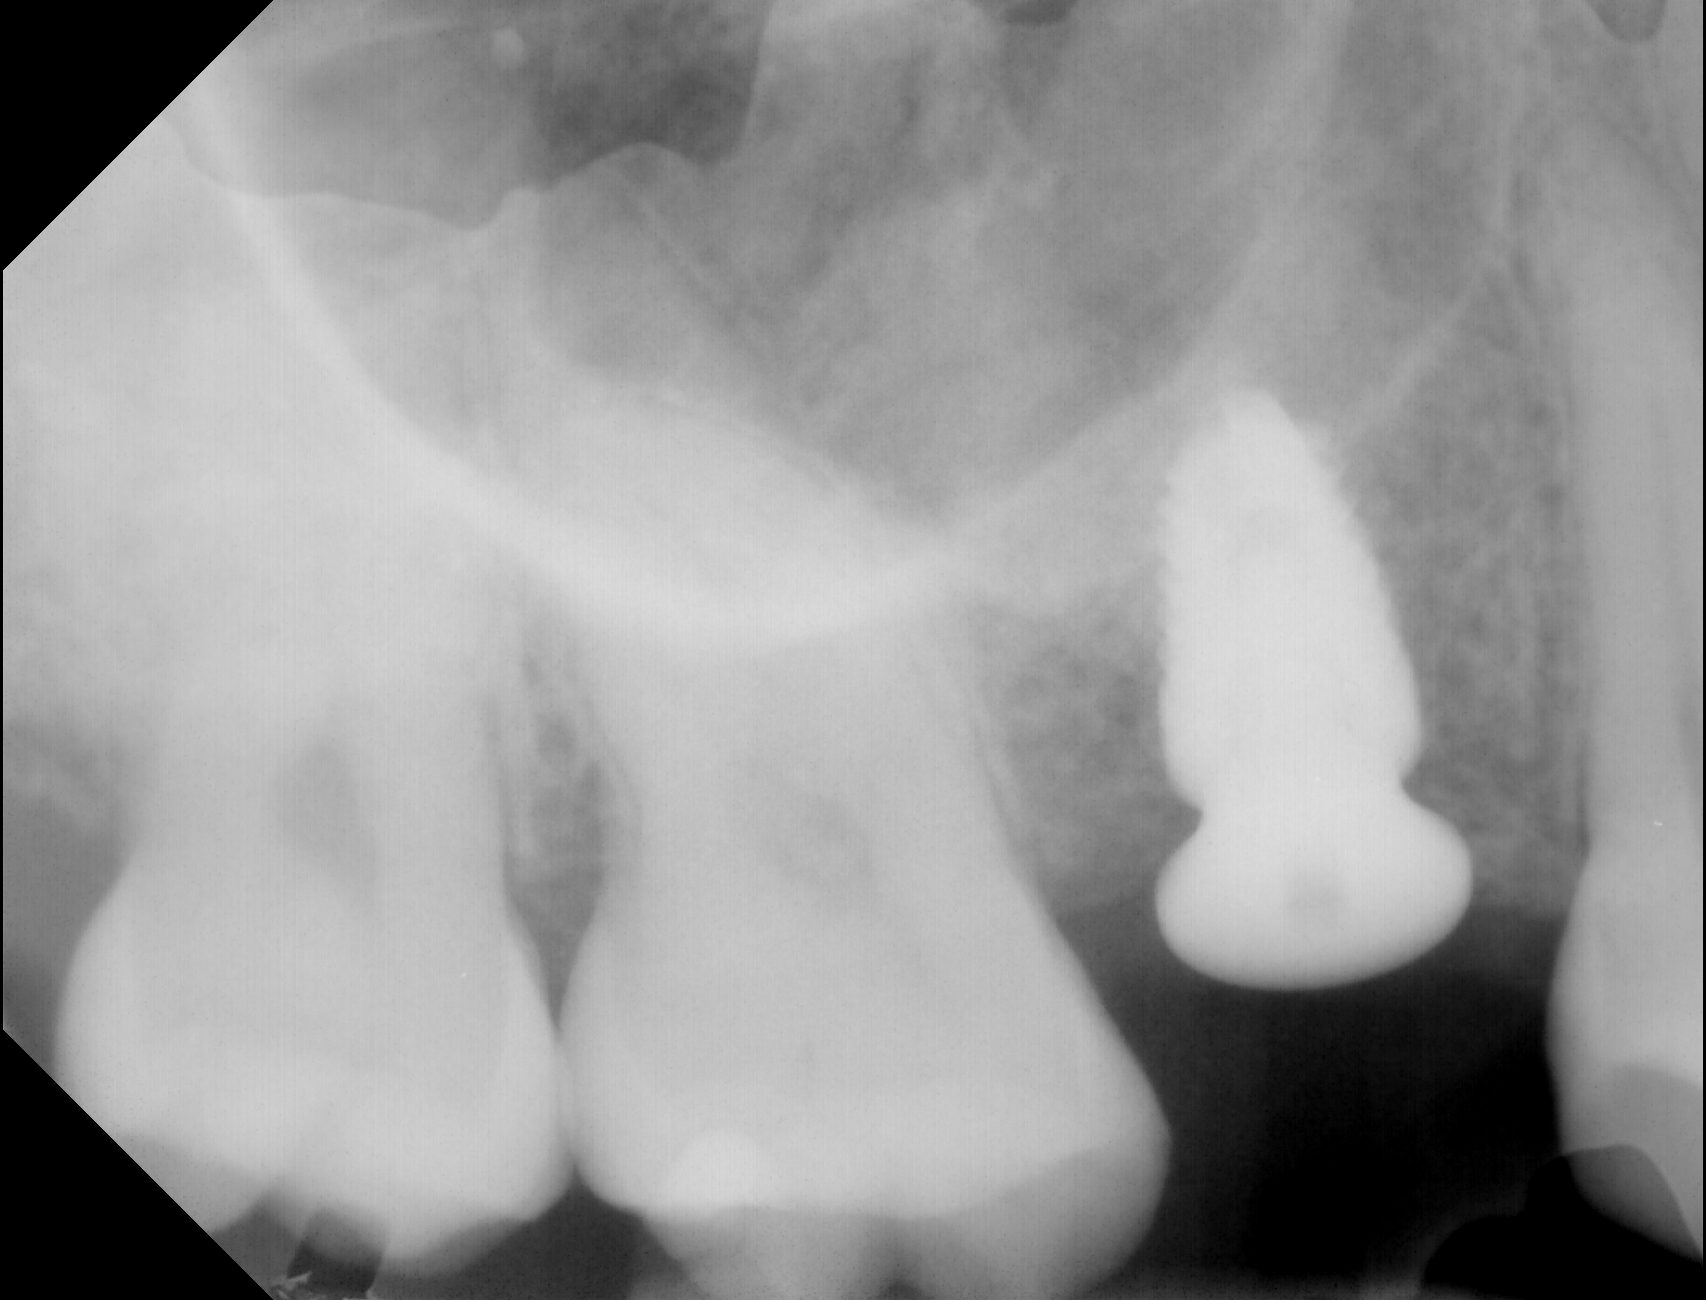

Here are 3 steps of installing implants

Here are 3 steps of installing implants

Here are 3 steps of installing implants

Here are 3 steps of installing implants

Here are 3 steps of installing implants